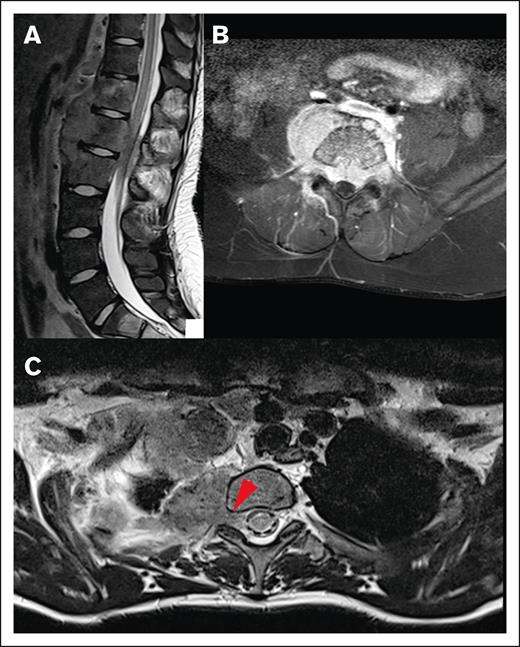

Different origins of CNS HL lesions. (A) Tumor originating from bone (vertebral body of T12, L1, and L2). (B) Unclear tumor origin but very likely bone, with circumferential involvement and an associated soft tissue component. (C) Paravertebral tumor mass of the upper thoracic spine infiltrating through the right neuroforamen, demonstrated by the red arrow, likely originating from soft tissue.

Baseline characteristics of the CNS lesions

None of the lesions involved the intra-axial CNS space. All lesions extended into the extra-axial CNS space from surrounding tissue. At the time of diagnosis, the majority of patients (82.2%) had a single lesion involving the CNS, whereas 4.4% had up to 3 discrete lesions in the CNS. The lesions extended into the thoracic spine (45.5%), sacrum (23.6%), lumbar spine (21.8%), cervical spine (5.5%), and skull (3.6%; Figure 2). In our cohort, 45% of lesions originated from adjacent bone and 40% from adjacent soft tissue. We were unable to determine the tissue of origin for 15% of lesions (Figure 3).